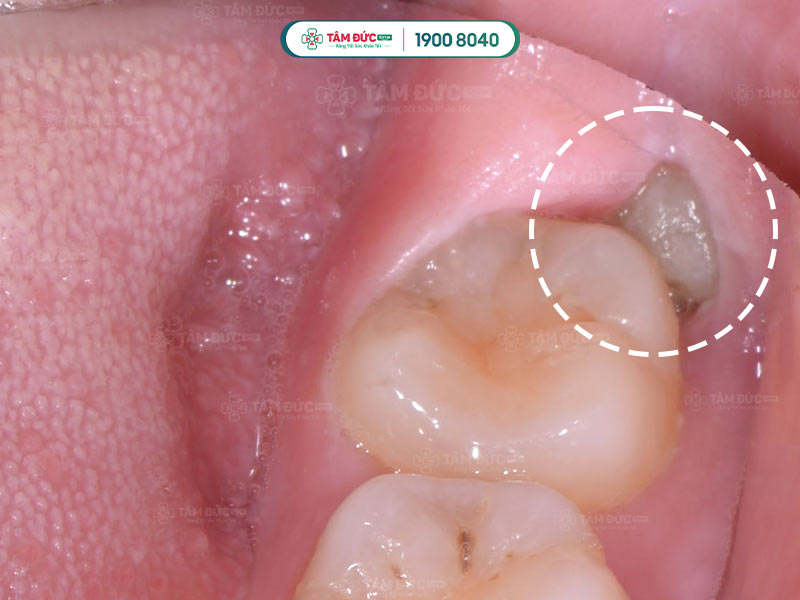

Răng khôn mọc lệch gây đau nhức và đâm vào răng số 7

Răng khôn không còn đủ chỗ mọc